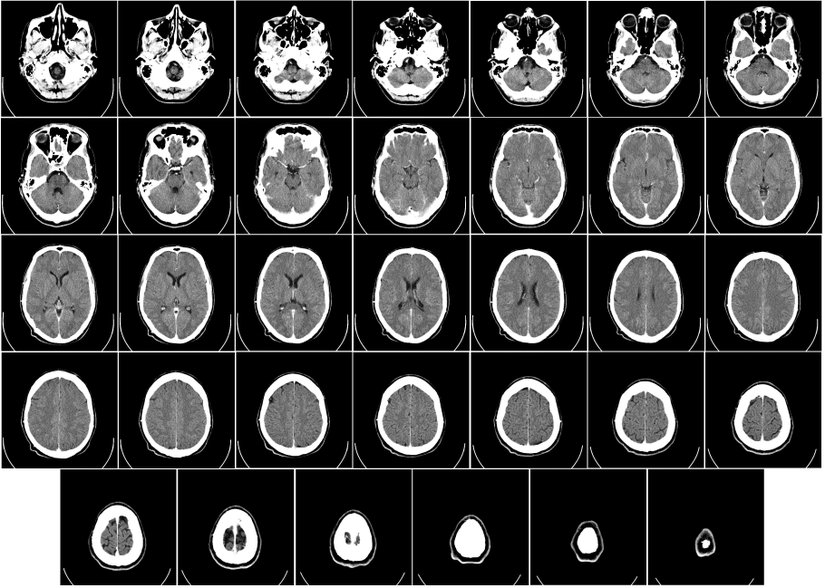

Obezite varlığında ise serebral kan akışındaki değişiklikler ilgi çekicidir. Şimdi, antropometrik obezite göstergeleri ile gri madde serebral kan akımı (CBFGM) arasındaki ilişkileri ve bu sonuçların daha yüksek fiziksel aktivite ile değiştirilebilme durumunu araştıran bir çalışmayı daha yakından inceleyelim.

İnceleyeceğimiz bu çalışma toplumda yaşayan İrlandalı yetişkinlerin 2009'da oluşturulmuş ulusal düzeyde temsili devam eden ileriye dönük bir kohort çalışması olan TILDA'nın bir parçası olarak yürütülmüştür (TILDA, çeşitli sağlık, ekonomik ve sosyal verileri toplayarak aralarındaki etkileşimi araştırır). Bu çalışma için 4039 katılımcıdan çok parametreli beyin MRI'ı istenmiş, toplamda 560 katılımcının MRI görüntüleri incelenmiştir. Araştırma için uyumlu olmayan katılımcılar elenerek 495 katılımcı ile araştırma gerçekleştirilmiştir.